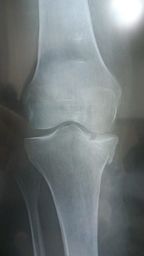

Après on voit quand même où est le souci mais j'ai quand même dit au mec que j'étais pas sûr de moi n'ayant pas l'expertise d'un radiologue ou d'un chir ortho.

Mais de toute façon on reçoit les comptes rendus des radiologues après c'est bien de regarder les images aussi mais encore faut t'il avoir le temps et les images